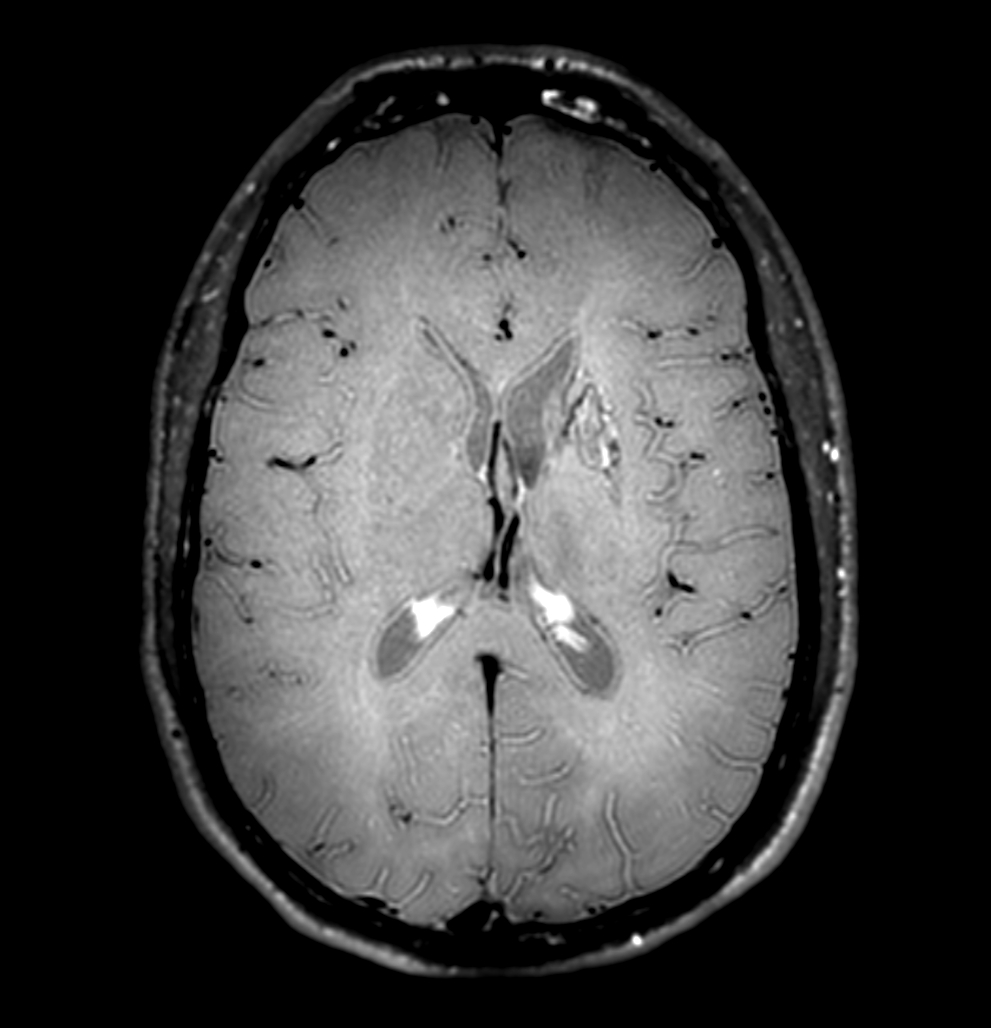

3D T1w TFE (post-gado)

-